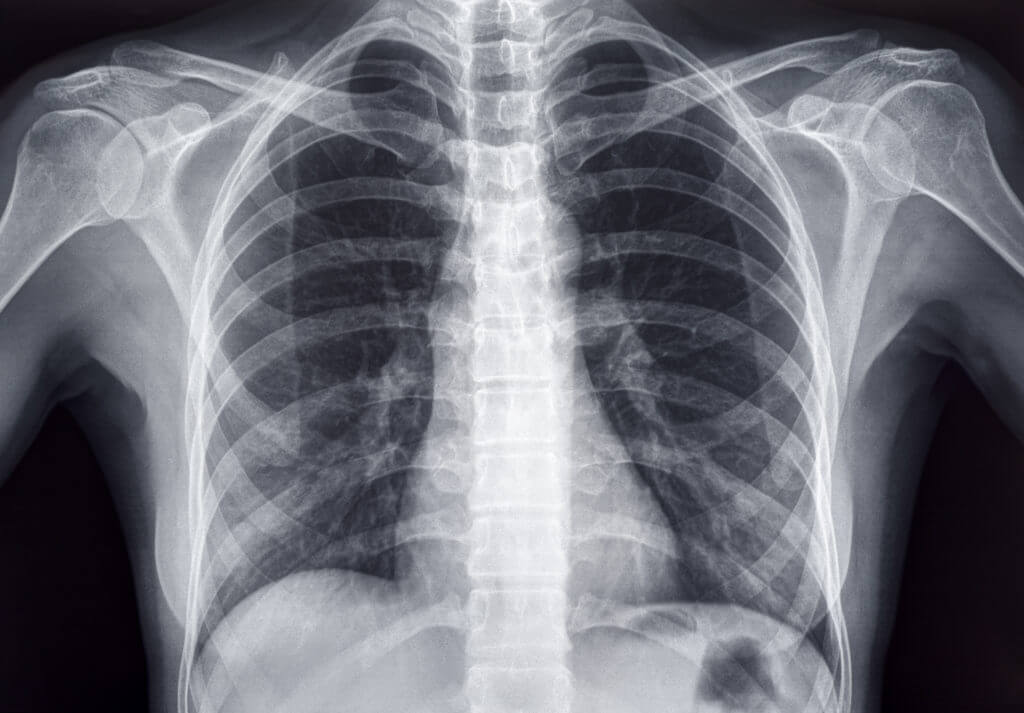

OSAKA, Japan — Artificial intelligence can determine a person’s “real” age simply by looking at their chest, according to a new study. Specifically, researchers in Japan say AI can tell a patient’s age after examining chest X-rays, marking a significant leap ahead in medical imaging. The breakthrough paves the way for improved early detection of several potentially deadly diseases.

Researchers at Osaka Metropolitan University developed the advanced AI model to use chest radiographs to accurately estimate chronological age. If a disparity exists between the AI-estimated age and the patient’s actual age, this could be a warning sign of chronic disease.

The research team, led by graduate student Yasuhito Mitsuyama and Dr. Daiju Ueda, first constructed a deep learning-based AI model to estimate age using chest radiographs of healthy individuals. They then applied this model to radiographs of patients with known diseases to analyze the relationship between the AI-estimated age and each specific disease.